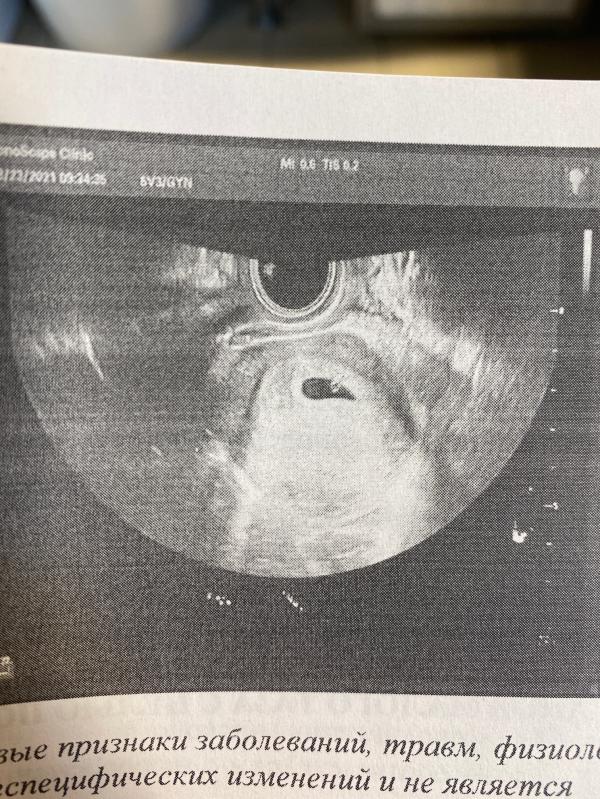

Такая кроха😻😻🌸

24.08.2021